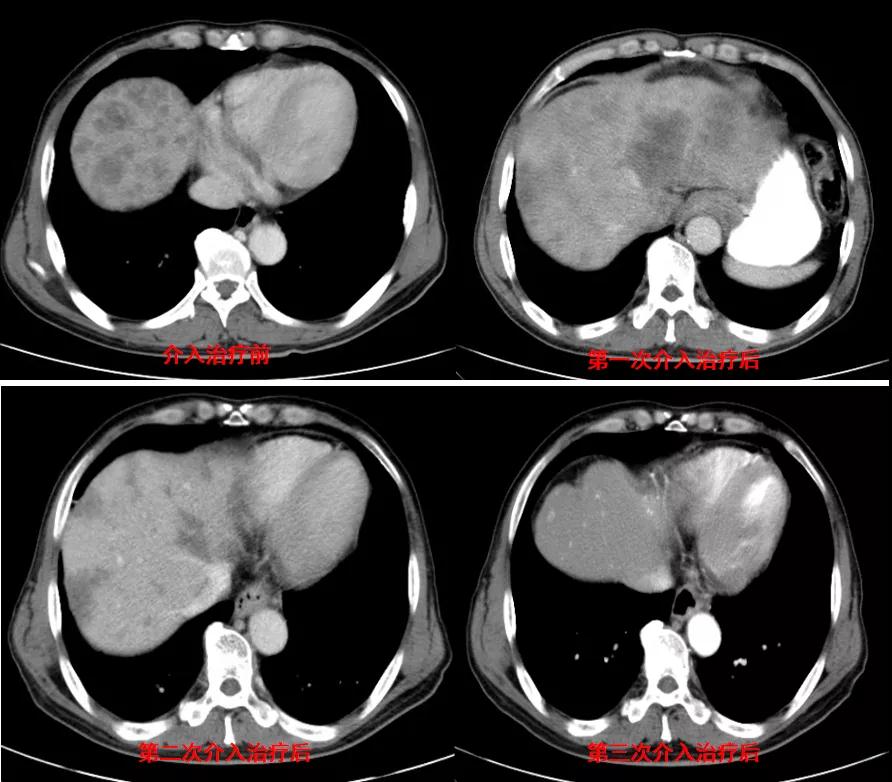

诊治经过:2020年12月16日患者行第二次经皮动脉化疗灌注栓塞术(铂类+氟尿嘧啶)治疗,并继续联合吡咯替尼治疗。结果见图3。

图3

讨论目的:第二次介入治疗后,患者肝转移病灶明显减少,针对少量肝转移病灶是否行射频消融治疗。

讨论:患者病灶进一步减小,病情控制好,治疗疗效显著且肝转移病灶大于3个,因此不建议行射频消融治疗,建议继续行介入联合靶向治疗。